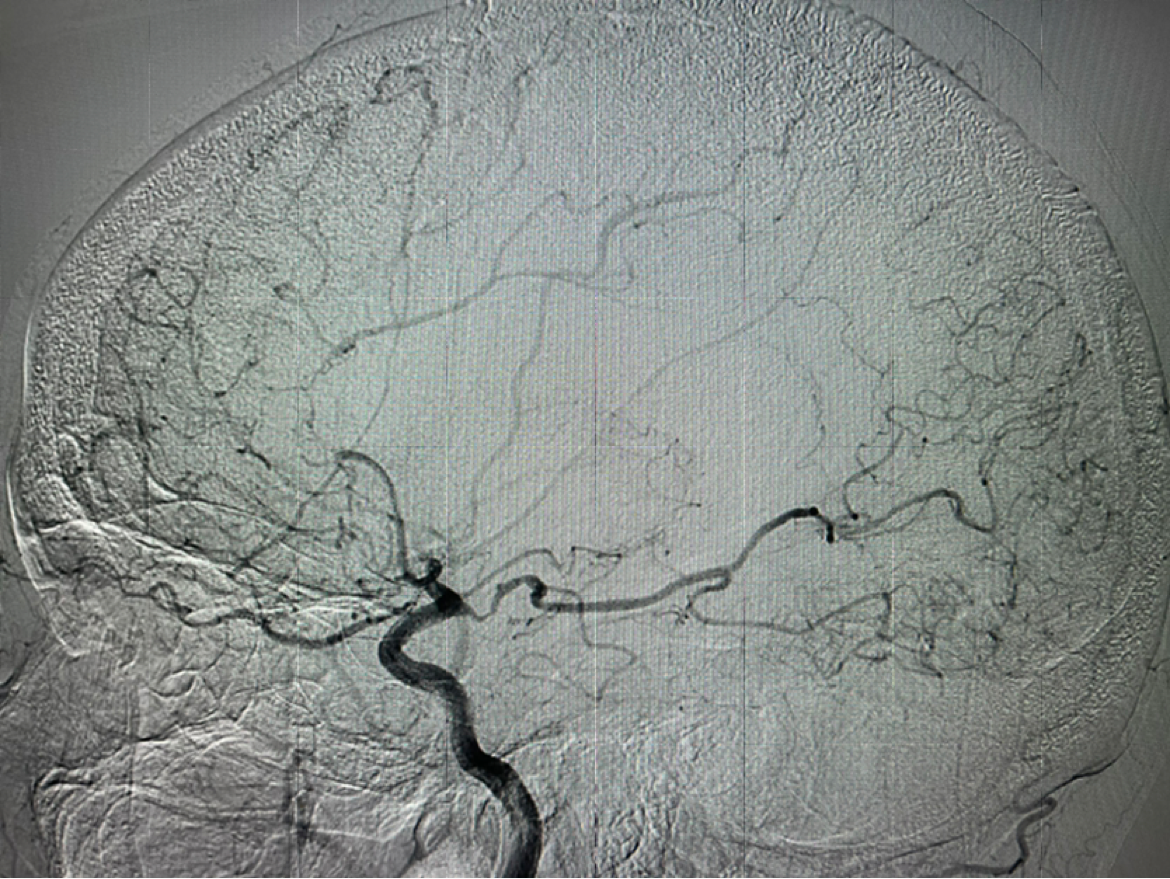

6F115c m中间导管到位后右侧工作位造影

支架植入后正位造影提示大脑中动脉开通良好